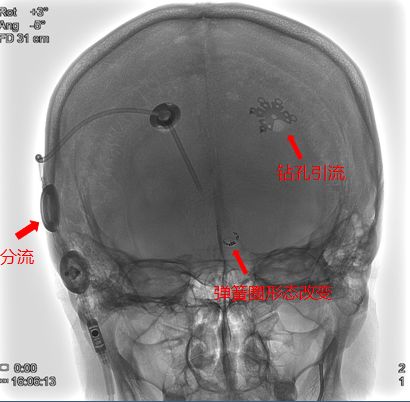

2018年2月13日:动脉瘤栓塞术后,行第一次开颅—钻孔引流术。

2018年4月7日:第二次开颅—行脑室腹腔分流术

钻孔引流术后CT

3-18 CT —脑积水

疑惑:第一次栓塞后,再次复查弹簧圈散开,原因?假性动脉瘤?